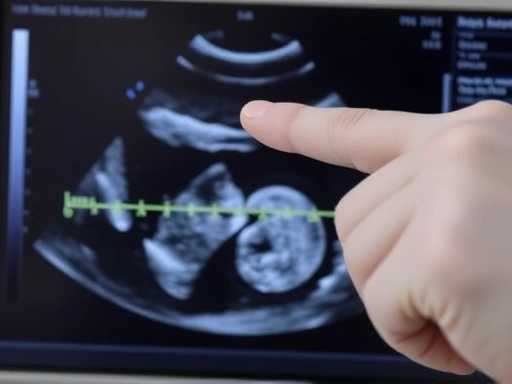

Close-up of a doctor's hand pointing to a fetal ultrasound image, highlighting the weight measurement

태아 체중 부족은 어떻게 진단하나요?

태아 체중 부족은 정기적인 산전 검진을 통해 진단할 수 있습니다. 초음파 검사를 통해 태아의 성장 상태를 확인하고, 임신 주수에 비해 체중이 낮은 경우 태아 체중 부족으로 진단할 수 있습니다. 또한, 도플러 초음파 검사를 통해 태반으로의 혈류를 확인하여 태반 기능 저하 여부를 확인할 수 있습니다.